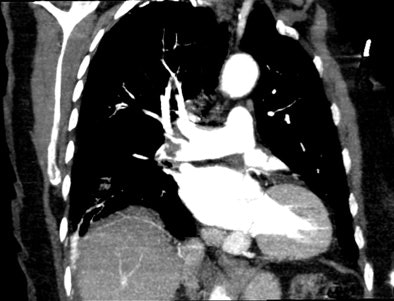

| An 81-year-old woman with acute chest pain and suspicion of acute pulmonary embolism. Short-axis images obtained at end-diastolic (above) and end-systolic (below) phase of the cardiac cycle using ECG-gated 16-slice CT. Right and left ejection fractions were measured at 43% and 41%, respectively. Note the variation of both ventricle volumes and myocardium thickness throughout cardiac cycle. On the same examination, slab MIP oblique reformatted images (bottom) revealed hypodensity in the right pulmonary artery and arteries of the right lower lobe consistent with acute pulmonary embolism. All images courtesy of Dr. Emmanuel Coche. |